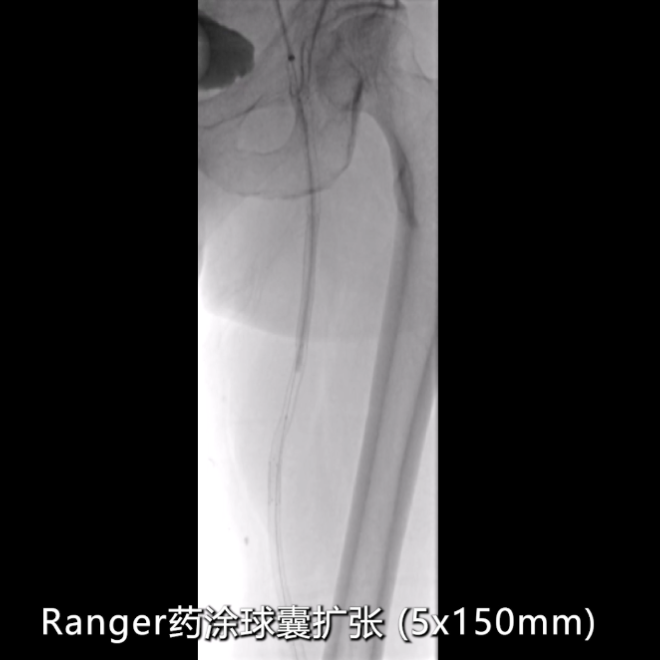

药物涂层球囊强化:

近端支架内病变采用5×200mmRanger药物涂层球囊扩张,强化抗再狭窄效果。